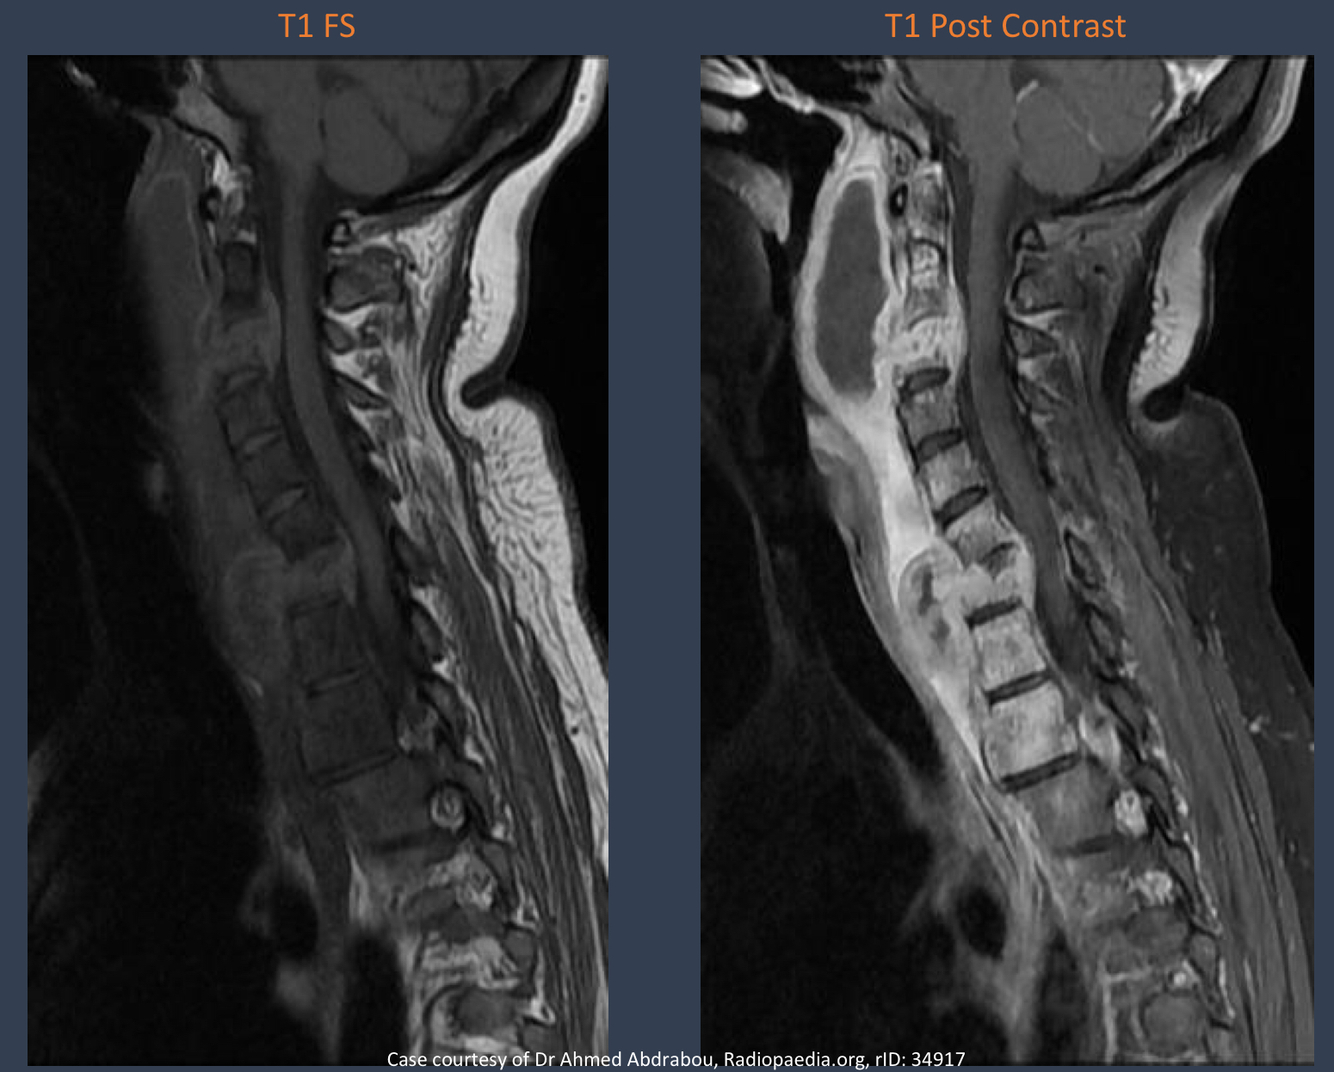

what is this imaging modality?

what is this condition? why?

MRI and T1 weighted CSF/bone is dark and fat appears bright

tubercular spondylitis “Pott’s Disease”; ???